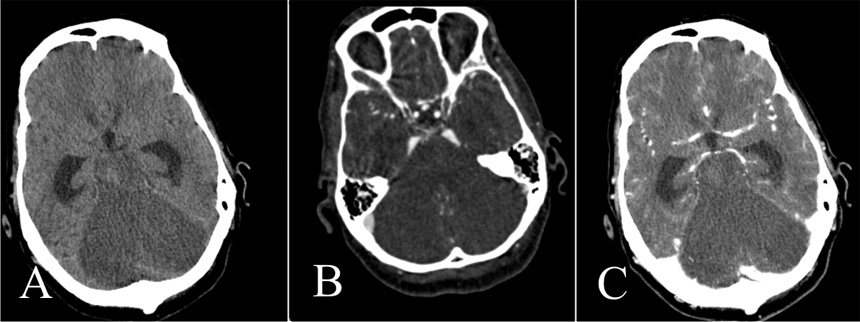

Figure 3

Non-contrast CT (A) and venous-phase CT (B): Opacification of the superficial temporal artery indicates sufficient contrast injection (Arrowheads). Note also opacification of an M4 segment artery on the right, a marker of some residual cortical perfusion. In this case, circulatory arrest could not be confirmed.

Figure 4

Unenhanced CT (A), CTA (B), and venous-phase CT (C).

Note normal opacification of the supratentorial vessels. Brain death could not be confirmed although there is extensive infarction of the cerebellum, pons and brainstem. The supratentorial ventricles are dilated.

One patient (table 2, no. 25) had extensive ischaemia of the cerebellum, pons and brainstem, the supratentorial territory, however, was nearly normally opacified in the arterial and venous phase (fig. 4) meaning that the criteria of circulatory arrest of the whole brain were not fulfilled. This is an example where the supratentorial brain may still be viable in context of law but the infarction of the brainstem leads to a clinically unreactive coma.